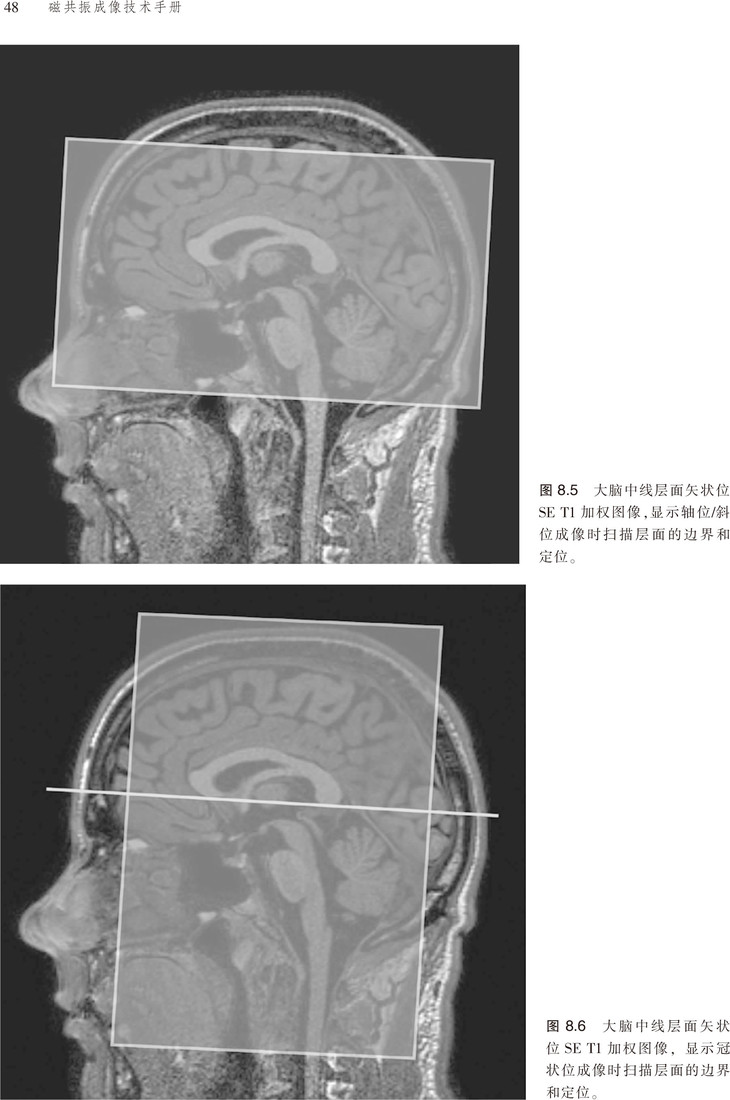

该书对脉冲序列、伪影、门控技术、预饱和技术等原理进行了讲解,且涵盖临床应用的相关参数,并就对比剂等以及受检者的安全性进行了分析。更为可贵的是该书不仅有应用解剖图谱,还有扫描的参照图,便于读者阅读,加深对书中内容的理解。